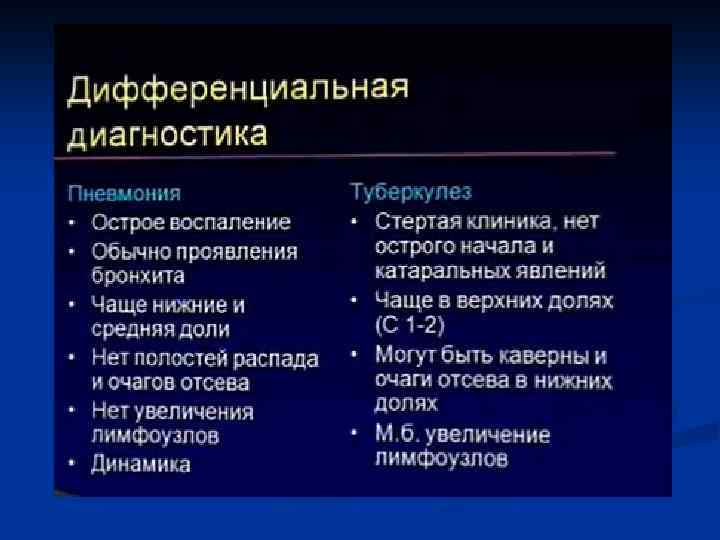

ИТАК, n Долевые и очаговые инфильтративные изменения обычно характерны для бактериальных пневмоний n Сетчатые интерстициальные изменения или сочетание инфильтративных и интерстициальных изменений типичны для пневмоний вирусной, микоплазменной, хламидийной и пневмоцистной природы, а милиарные поражения — для туберкулеза легких, генерализованного сальмонеллеза, грибковых поражений. n Инфильтративные или интерстициальные изменения в сочетании с лимфоаденопатией типичны для туберкулеза легких и пневмоний, вызванных грибами, микоплазмой, хламидиями, вирусами кори и ветряной оспы.